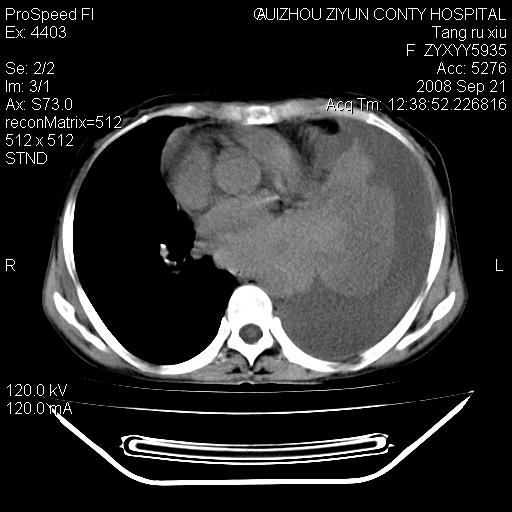

f、57岁,上腹痛.2月,近来胸闷。2月前在外院摄胸片示左侧胸腔少量积液。

(患者腹痛入院,欲吐,临床医生说禁饮,所以没有口服对比剂)

考虑----左侧胸腹腔积液----压迫性肺不张----心包积液---肝脏多发低密度影-----穿刺抽液后复查

左侧胸壁见一结节影,肝脏多发低密度影,左侧胸腔大量积液。建议增强

1)考虑左侧肺癌侵犯纵隔,左侧胸膜、肝脏及腹膜后淋巴结转移。2)左侧胸腔积液。3)心包积液。

肝脏大小形态尚可,其实质内可见多发大小不等的低密度影,边缘模糊。肝门区结构紊乱,腔静脉腹主动脉旁可见多发软组织密度影,部分融合成团块状,并向下延伸。胰腺及十二指肠结构显示不清。腹腔内脐后肠管走形僵硬,管壁可见增厚。盆腔内可见多个淋巴结影。所扫层面左侧胸腔可见大量弧形水样密度影,其内侧可见被压缩的肺组织影。左侧胸壁可见一小结节样软组织密度影,边缘模糊。心脏纵隔向右侧移位。心脏包膜内可见囊样低密度影,其内侧心房室周围可见一圈气体样密度影。纵隔内大血管旁可见多发软组织团块影,部分融合。

1.腹膜后淋巴瘤侵及肝脏,肺内及纵隔内多发转移。2.左侧大量胸腔积液并压缩性肺不张。3.心包脓肿可能,转移不除外。4.脐后局部肠管管壁增厚,考虑炎症可能,肿瘤不除外。